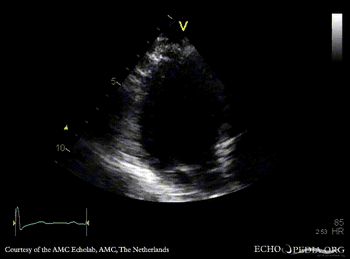

E00737.gif E00738.gif

PSAX with Color Doppler: high velocity flow in LVOT A3CH: subvalvular membrane